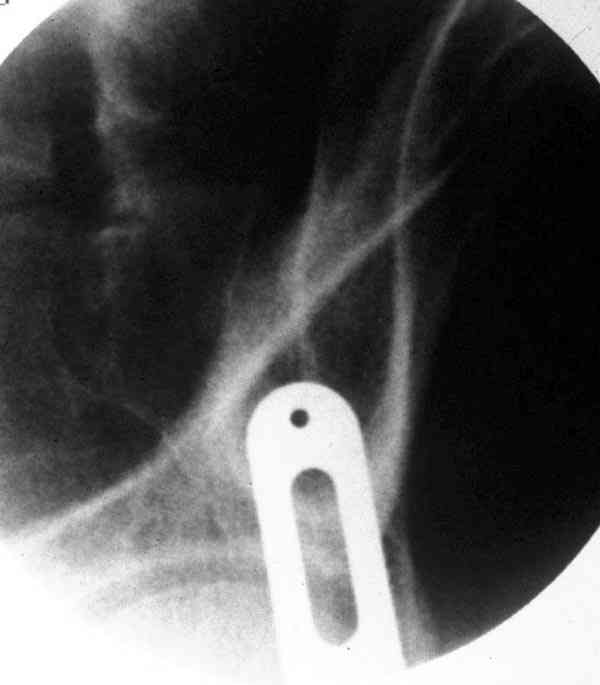

При свежем случае показана фиксация передней колонны к задней (снимки), компрессирующим винтом минимальным перкутанным методом по супраацетабулярной линии и в зависимости от состояния КПС.

iliac view

obturator tear drop view

obturator view

Стандартные снимки ацетабулума по Judet и снимки таза (инлет и оутлет) подскажут дальнейшую тактику по нагрузке.